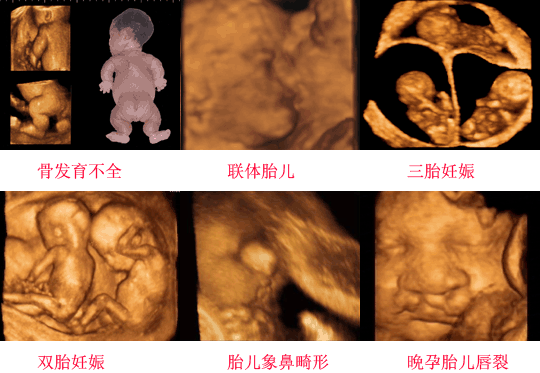

四维彩超的全称是四维彩色超声诊断仪,是世界上最先进的彩色超声设备。四维彩超能够表面成像,可以更佳清晰的查出来胎儿的四肢发育是否畸形,脑膜膨出,是否唇腭裂、脊柱裂等先天畸形,及早发现及早的做出解决方案。

4、胎儿是否畸形:彩超检查时发现胎儿畸形的一个重要的手段。一旦发现胎儿畸形,就可以及时终止妊娠,通常孕妇在妊娠22-26周做彩超可以筛查胎儿是否畸形,因为这个时段的胎儿各个器官都已经发育成型形,比较容易看出有没有畸形。所以做彩超检查十分重要。